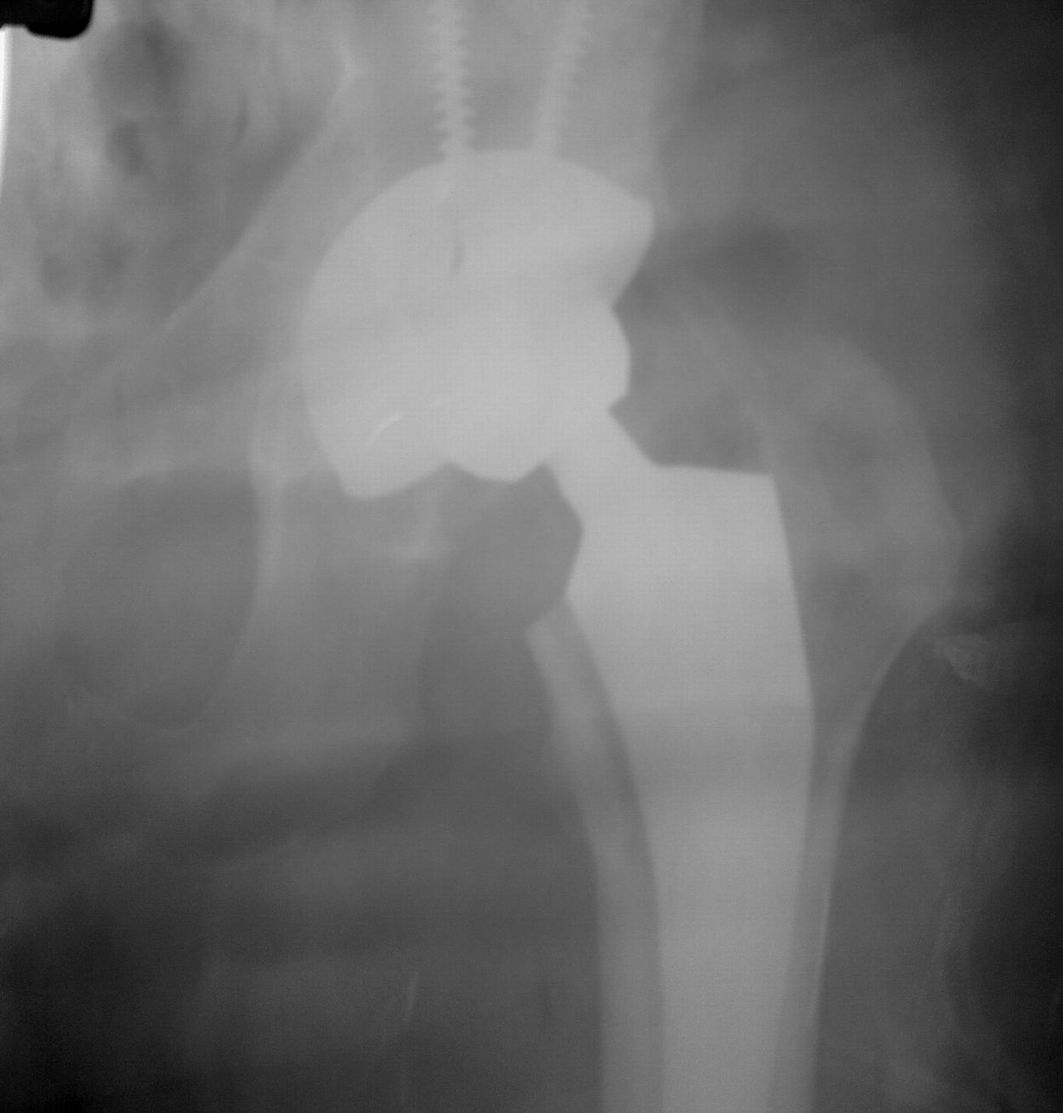

Сегодня все-таки выполнили ревизию вертлужного компонента. Действительно, чашка держалась только по окружности, относительно легко удалилась. Так что тактику считаю правильной, ибо ловить при такой установке особо нечего было. Нестабильность в блишайшее время была бы обеспечена. Снимки после переустановки в приложении. Качество, конечно не ахти какое, это сделано на столе на плохом аппарате. Посадка проконтролирована визуально через центральное отверстие. Головку не снимали, оставили короткую. Если до ревизии длина левой ноги была +1 см, то после D=S. Теперь осталось молиться, чтобы не было осложнений. Вроде бы все прошло не травматично.

Имя     : 01062010120.jpg